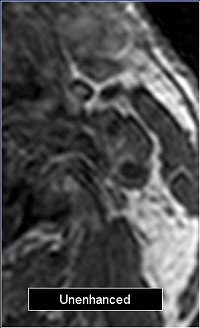

The mean score for plaque enhancement on unenhanced and enhanced images was 1.44. On subtracted images, the mean score was 2.44.

![]() |

| Above, the unenhanced image. Below, the enhanced image and the MRA showing plaque enhancement, which is more evident after electronic subtraction. All images courtesy of Dr. Francesco Sardanelli. |

Plaque enhancement was evaluated on axial images by two radiologists in consensus on a four-point scale (0 equaled no enhancement; 3 equaled clear enhancement). They looked at enhanced, unenhanced, and electronic subtraction images.